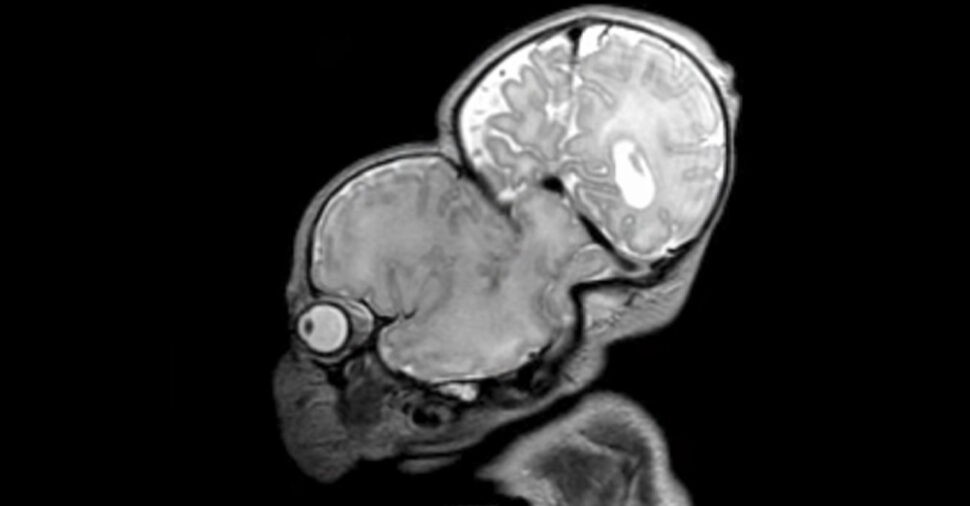

3D printing is reshaping medicine, and its impact is most evident in the growing use of anatomically accurate surgical models. In a landmark Israeli operation, these models were pivotal in separating craniopagus twins—children conjoined at the skull—who had a very low chance of survival.

Leading the effort was Dr. Noor Ul wase Jeelani, a Kashmiri‑born pediatric neurosurgeon, who directed a multidisciplinary team at Soroka‑University in Israel. The pre‑operative plan integrated tools from 3D4OP, Surgical Theater, and Stratasys, while scans from CT and MRI machines were processed with Materialise 3‑Matic medical software to produce life‑like models.

These highly accurate replicas allowed surgeons to identify blood vessels, dura mater, skin, and bone in a tactile format identical to what they would encounter during surgery. The models could be positioned to match the twins’ orientation in the operating room, enabling rehearsal for both surgical and anesthesiology teams.